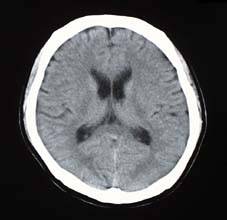

腹 部 頭 部 頭 部

頭部3DCTA(CT血管造影)